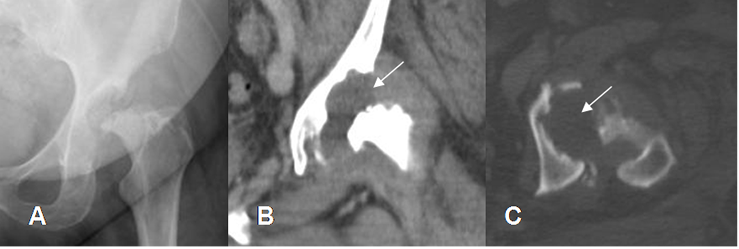

Fig 50. Sinovitis villonodular pigmentaria.

A: Rx cadera AP. Sinovitis avanzada, con reabsorción de la cabeza femoral y la cavidad acetabular.

B: TAC reconstrucción coronal y C: TAC axial. Destrucción de la cabeza femoral y la cavidad acetabular, con tejido blando que ocupa el espacio articular. Flechas).